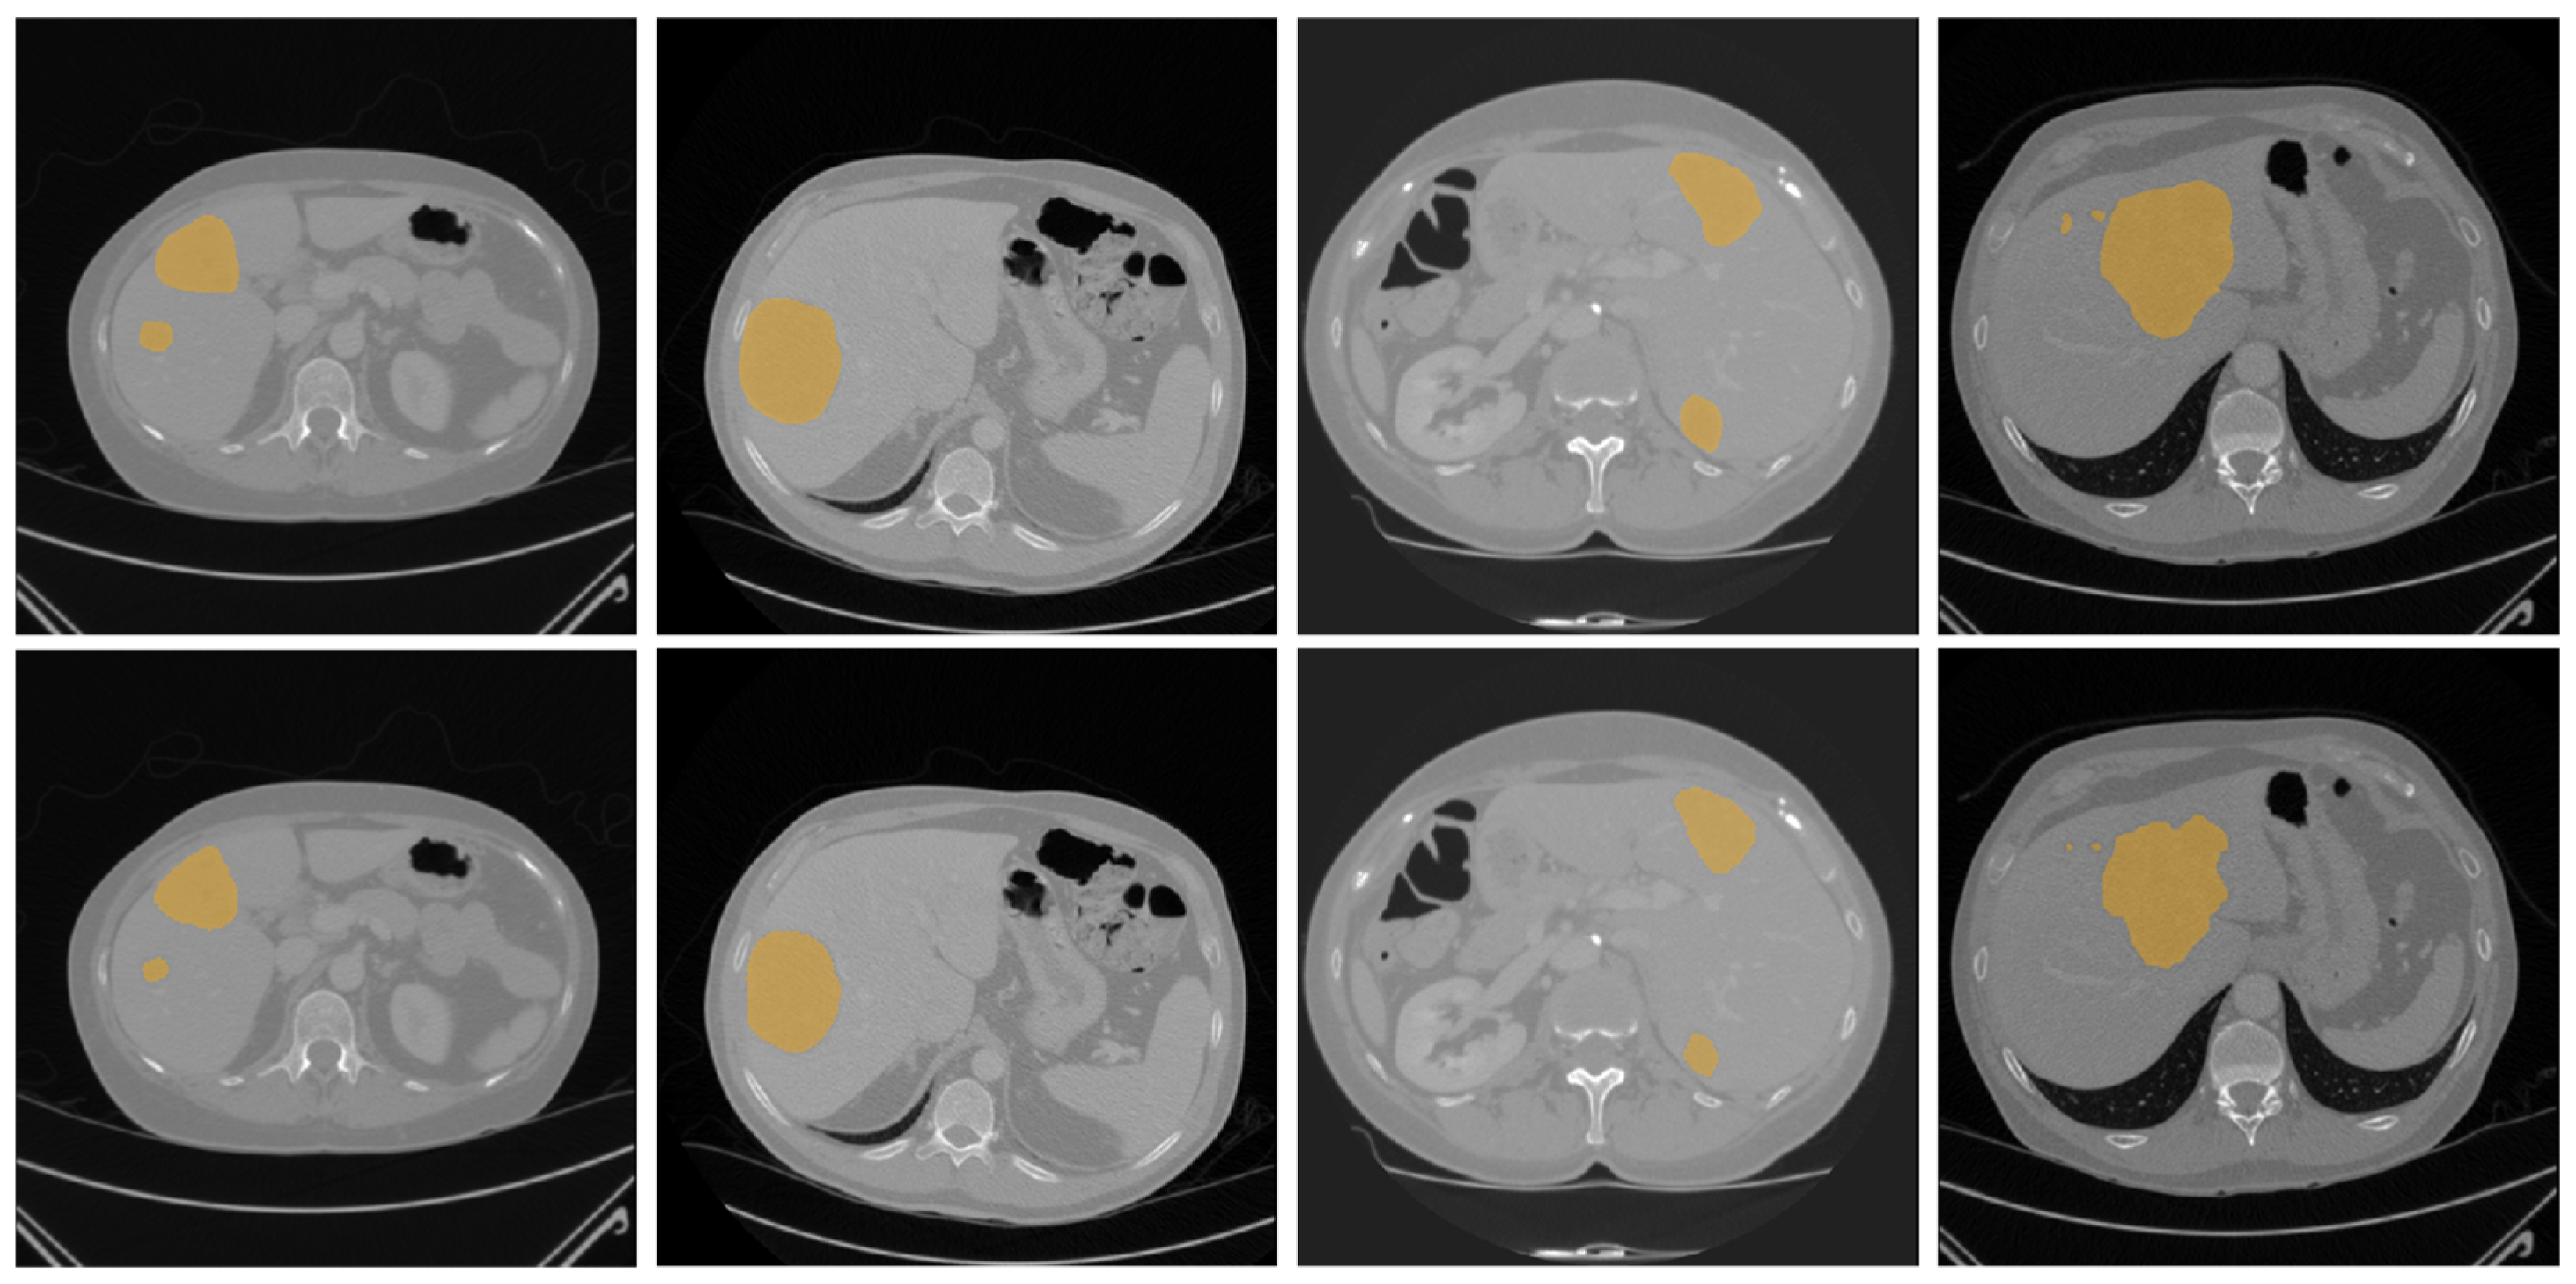

Preprocessing was performed to normalize the Hounsfield Unit values of all CT scans to a range of −250 to 250 to enhance the visibility of the liver and tumor regions, as shown in Figure 1. All CT scans were resized from 512 × 512 to 256 × 256 to reduce computational cost. The same data augmentation strategies as G-UNERT++ [19], such as random rotation of 90, 180, and 270 degrees, random scaling, random mirroring, and random intensity shifting were applied.

Figure 1. CT image processing performed to enhance the visibility of the liver and tumor regions by normalizing the Hounsfield Unit values to the range of −250 to 250: (a) the original CT slice; (b) the enhanced CT slice.